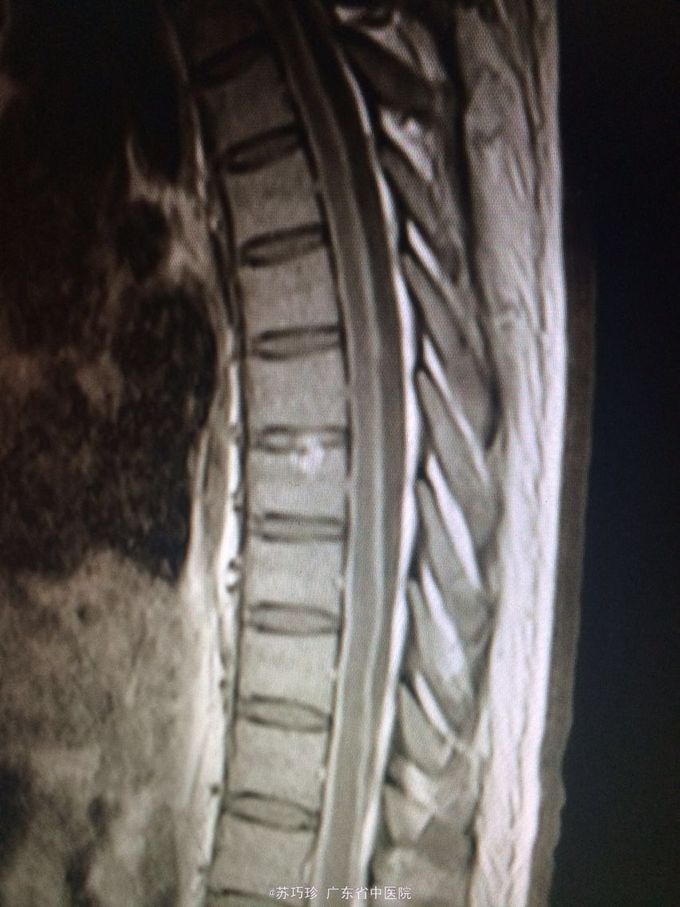

查体:心肺腹(-)。视物重影,右眼外展不到位,T8以下痛、触觉减退,右上肢肌力4级,双下肢肌力0-1级,双下肢肌张力降低,双下肢腱反射消失,腹壁反射消失,颈抵抗约3横指,克氏征(+)。 辅助检查:血常规、肝肾功能及心电图、腹部B超检查未见异常。胸部CT+增强:左肺上叶下舌段慢性炎症;双侧少量胸腔积液,双肺下叶含气不全。头颅+胸椎+腰椎MR平扫+增强:双侧额顶颞枕叶脑沟、双侧侧脑室室管膜、双侧小脑半球软脑膜、脑干软脑膜、颈胸腰段脊髓软脑膜、马尾异常强化影,结合临床考虑炎症性病变;左侧颞叶、左侧丘脑、左侧内囊后肢异常弥散,提示急性脑梗塞灶与感染灶相鉴别,建议复查;脑室系统改变,考虑脑积水;T7/8椎间盘变性,邻近椎体许莫氏结节形成;胸腰椎骨质信号未见异常;骶管囊肿。心脏彩超:EF:64%,主动脉瓣少量返流,左室顺应性减退,少量心包积液。